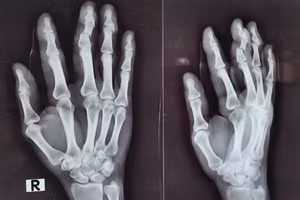

Dùng dao bổ mít, bé trai 6 tuổi đứt lìa 3 ngón tay 09/10/2024 11:53 GD&TĐ -Cùng bạn lén dùng dao bổ mít, bé trai 6 tuổi bị đứt lìa 3 ngón tay ở bàn tay trái.

Cấp cứu thành công bệnh nhân gần đứt lìa ngón tay 05/03/2024 08:58 GD&TĐ - Mới đây, Bệnh viện Đa khoa Xuyên Á Tây Ninh đã tiến hành nối lại thành công ngón tay đứt gần lìa và gãy hở phức tạp cho một trường hợp tai nạn lao động.

Cổ vũ quá nhiệt, cổ động viên mất... 1 ngón tay 05/11/2021 16:21 GD&TĐ - ‘Cổ vũ quá cuồng nhiệt’ khiến một người hâm mộ đội bóng Ngoại hạng Anh West Ham… mất một ngón tay.